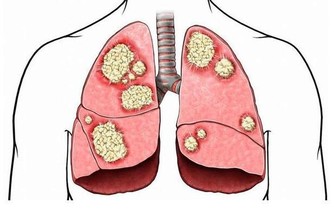

口腔的健康狀況也可以很好地預示心血管是否出現了問題。人體口腔中充滿了細菌,同時存在有益菌和有害菌。損害人體的細菌可以從口腔進入血液,並引起血管炎,嚴重時會導致心血管疾病。心臟外科專家稱,牙齒脫落和牙齦發炎(牙周炎)是心髒病的先兆。